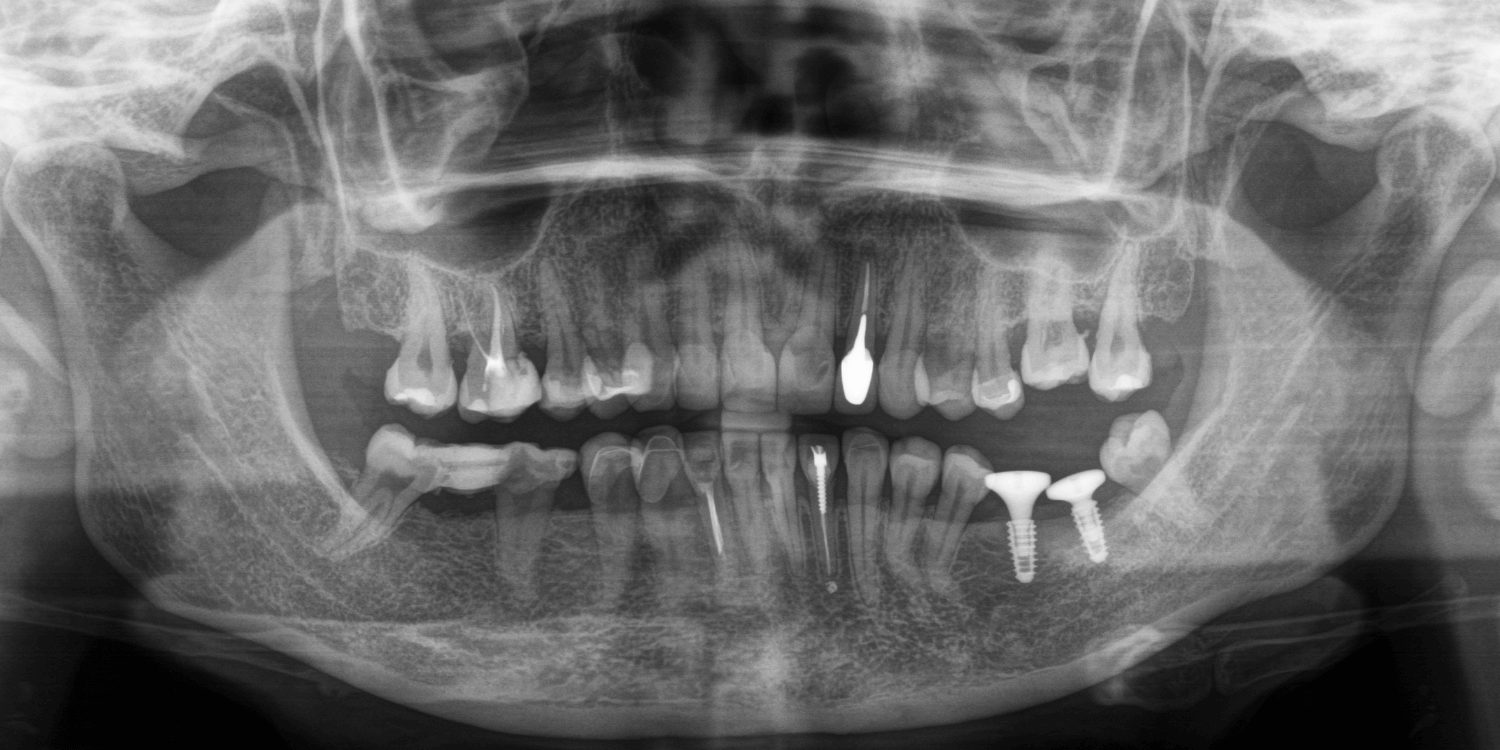

Впервые мы встретились с пациенткой примерно год назад. Тогда она обратилась к нам в клинику для проведения профессиональной гигиены полости рта и были жалобы на отсутствие зубов 6 и 7 на нижней челюсти слева. После КТ-исследования и осмотра обнаружили, что некоторые зубы (ранее протезировавшиеся) уже депульпированы. Практически все зубы были покрыты коронками, полукоронками и винирами. Относительно старые, но в удовлетворительном состоянии. Объем костной ткани позволял провести имплантацию зубов. Предложили установить зубные импланты методом двухэтапной имплантации на место отсутствующих зубов с дальнейшим протезированием цельнокерамическими коронками.